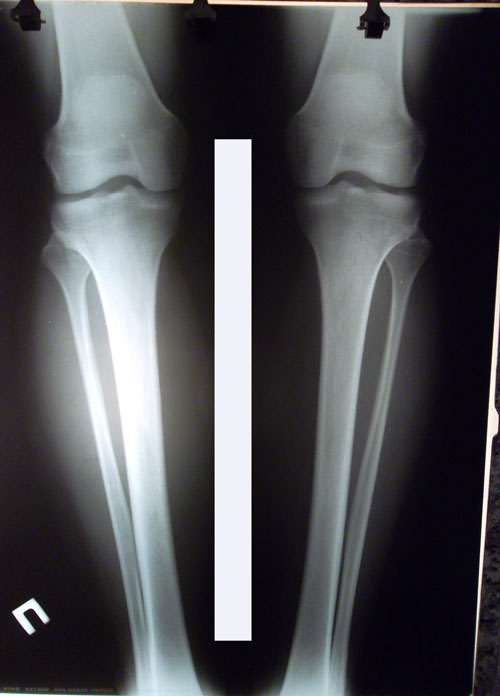

рентген в 60 дней.

Сращение идёт хорошо. Делаем рентген в 90 дней и готовимся к снятию.